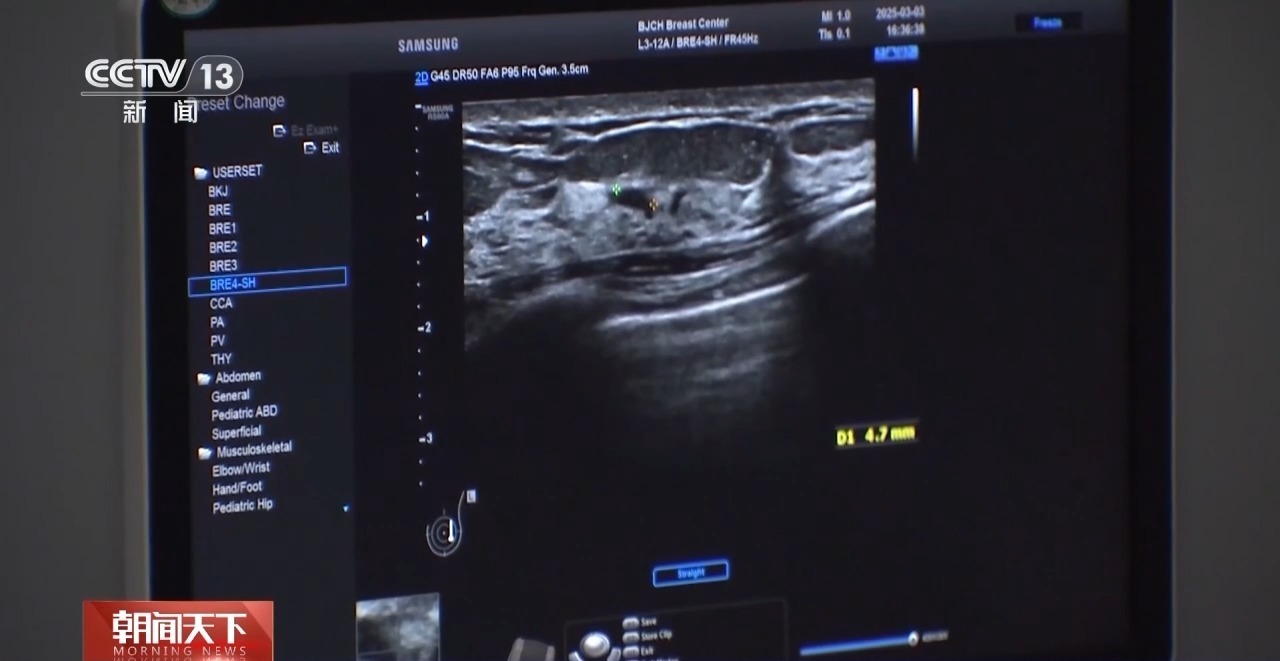

北京大学肿瘤病院乳腺癌珍重疗养中心主任大夫 范照青:一般来说咱们保举40岁以上的女性,1到2年作念一次钼靶影相,也保举女性一又友每年至少作念一次乳房的超声查验。钼靶查验有可能会发现极早期的乳腺癌,也即是说所谓的原位癌,它一般还莫得发展成浸润癌的时刻,是不会酿成调整的,也即是说不班师胁迫生命的阶段,咱们把它发现赶早解决掉。

钼靶和超声,是当今我国乳腺癌筛查的主要查验门径。两项查验,各有优劣,40岁以下的女性,一般来说,更适合作念超声查验。

北京大学肿瘤病院乳腺癌珍重疗养中心副主任大夫 霍苓:(超声查验)领先是莫得放射,然后安全性好,是以不同庚纪阶段的女性,年青女性妊妇,还有需要频繁查验的女性皆是不错频繁作念的。钼靶是一个X线查验,它是有放射的,作念的时刻会把病东说念主的乳房所有这个词这个词夹成一个片状,是以病东说念主的耐受进度也会差极少。

天然超声莫得放射,但关于渺小钙化,钼靶查验的明锐性更高。